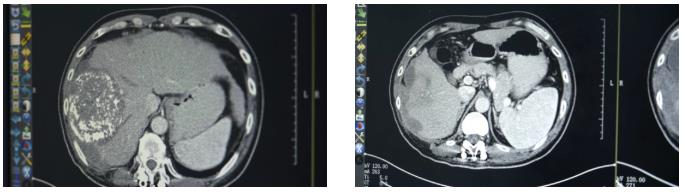

“吃了药,打了针,不怎么疼了,能吃饭能睡觉了。”几个疗程后,勇哥的生活质量明显改善。复查结果显示肿瘤得到控制,甲胎蛋白降至1.8万ng/ml。考虑到肝脏上病灶负荷太大,且紧靠周边,出血风险比较高,李红梅主任还是建议他进行肝动脉灌注化疗术(HAIC)。

第三次回院复查时,勇哥的甲胎蛋白已降至800多,CT显示肝癌及肝内多发转移瘤、双肺转移瘤及大网膜转移瘤都较前缩小,无新发病灶,病情评价为稳定(SD)。“这次做介入治疗时,医生告诉我肝上肿瘤基本没有活性了。”勇哥的声音中带着久违的轻松。